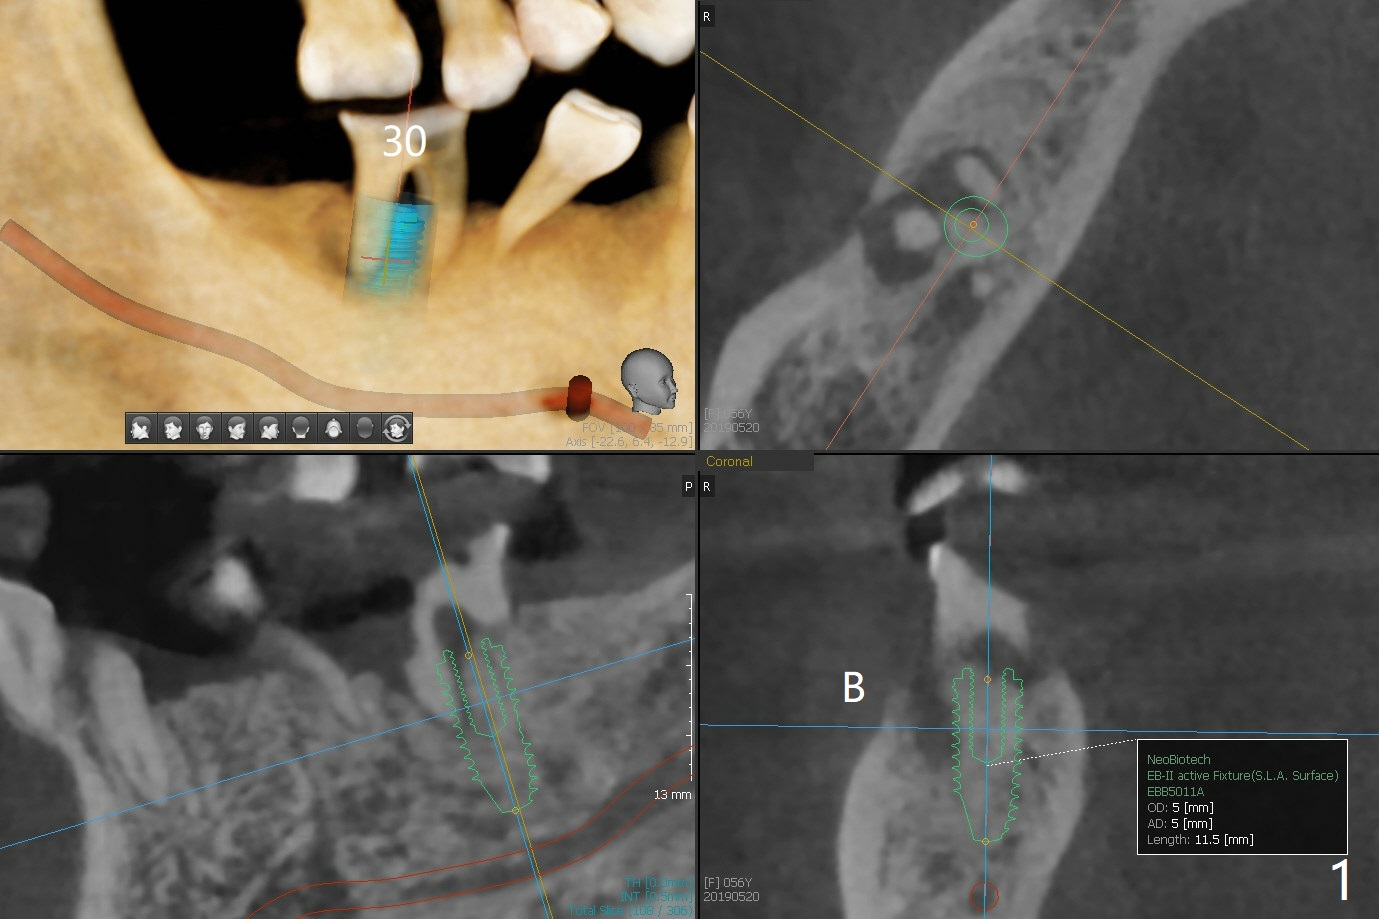

A 56-year-old woman does not want implant FPD at #18-20 six months post #18 and 20 implant placement. She agrees not to save the teeth #29 and 30 (Fig.1,2). An implant will be placed at #28 (Fig.3).